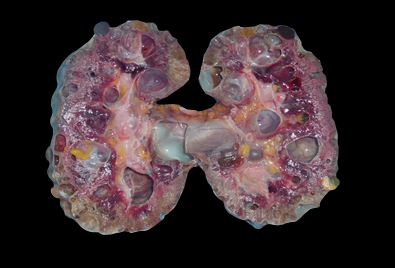

다낭성 신종이 발생한 신장 단면

성인이 된 후에 좌우 신장에 수많은 낭종(물집)이 발생하고 점차적으로 신장 기능이 감소하여 신부전 상태에 도달하는 병이다. 유전병의 일종이며, 두 가지 유전 형태(제1형과 제2형)가 알려져 있다. 보통 20세가 넘어가면 좌우 신장과 간, 췌장 등에 여러 개의 물집이 발생하기 시작하여, 나이가 들면서 물집의 크기와 개수가 증가하고, 40~50대에 이르면 수많은 물집으로 인해 신장 기능이 감소하여 투석을 받거나 이식을 받아야 한다.

20대에는 낭종의 개수가 적고 크기가 작아 증상을 느끼지 못하는 경우가 많으며, 30대 이상에서는 낭종이 커지면서 신장이 커다란 혹으로 만져지거나 배가 불러온다. 혈압이 높게 측정되는 고혈압이 흔히 나타나고, 신장 위치에 해당하는 좌우측 옆구리 부분이 아프다. 소변이 붉게 나타나는 혈뇨가 나타난다. 낭종 안으로 출혈이 되기도 하고 신장에 돌(요석)이나 방광이나 신장의 세균성 감염도 흔히 나타난다. 30대 후반부터 50대에 신장 기능이 감소하기 시작하며, 신장 기능이 10% 이하로 감소하면 투석이나 신장 이식을 받아야 한다.